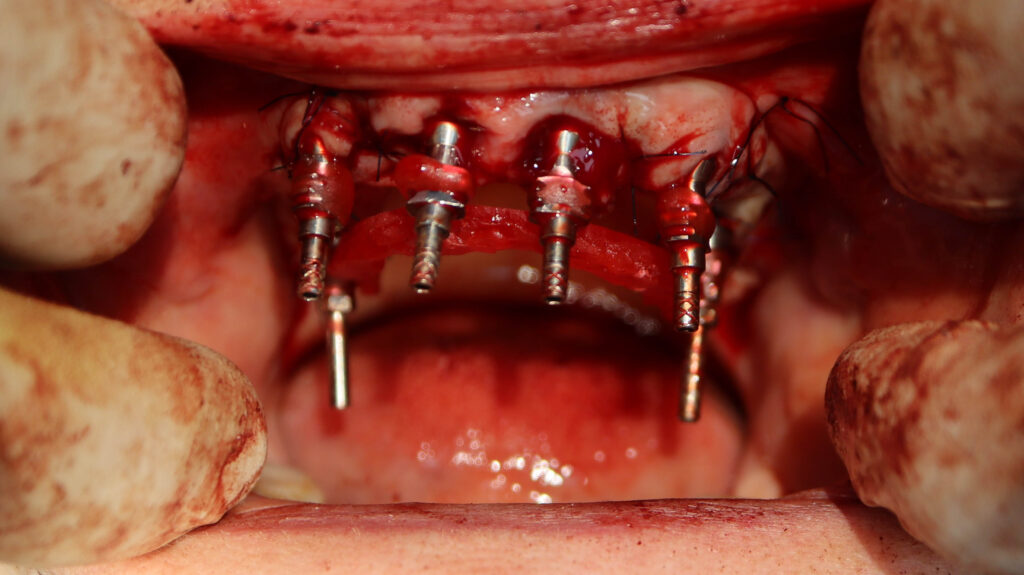

Это фото может содержать тяжелый для восприятия контент

процесс имплантации

На верхней челюсти были удалены зубы, которые находились в неудовлетворительном состоянии, проведена комплексная имплантация по системе All-on-6, установлены 4 имплантата Megagen AnyOne и 2 скуловых имплантата NeoDent.